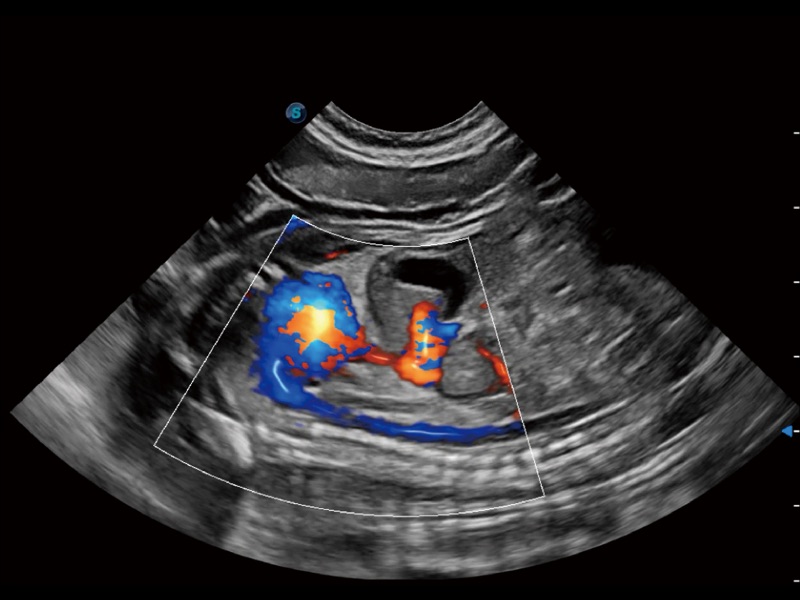

通過創(chuàng)新的 Matrix E自適應(yīng)濾波器和超長(zhǎng)時(shí)間域算法,極大提升超低速微細(xì)血流的檢出能力,同時(shí)更精準(zhǔn)地濾除軟組織和噪聲信號(hào),為獸用醫(yī)生提供以往無法通過常規(guī)血流獲得的疾病診斷信息。

通過色彩血流和實(shí)時(shí)寬景相結(jié)合,可觀察到完整的靜脈或動(dòng)脈的血流,方便醫(yī)生檢查。實(shí)時(shí)掃查過程中,如有任何操作失誤也可以很容易地進(jìn)行回掃擦除,而不會(huì)中斷掃查。